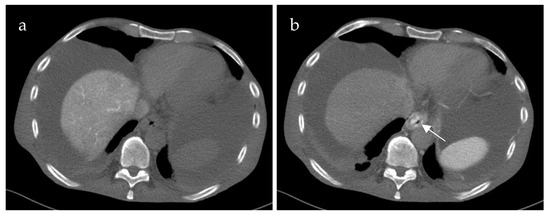

3.3. CT-SMPG Compared to CECT

Additional CECT in the portal venous phase was available in 18 of 21 patients. Table 1 summarizes the diagnostic differences of CT-SMPG and CECT concerning detection of thrombosis of splanchnic veins (SMV, SV and confluence) and varices. CT-SMPG and CECT were quite similar in detecting PVCT, SMV and SV thrombosis whereas CT-SMPG was superior to CECT in detecting varices, gastropathy and venous congestion. Figure 2 shows an example of the same patient comparing CECT and CT-MPG.

Figure 2. 70-year-old female patient with portal hypertension due to chronic portal vein thrombosis. Axial images of contrast-enhanced computed tomography (CECT) (a) and computed tomography mesenterico-portography (CT-MPG) after contrast injection into the superior mesenteric artery (b). The CECT image shows diffuse contrast enhancement of the gastric wall (a) (white arrow). CT-MPG detects the partial hyperperfusion of the gastric wall (white arrow) and the cavernous transformation of the portal vein (white arrowhead (b)).